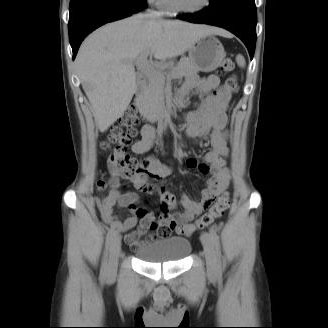

CT検査は様々な方向からX線を当て体内の水分や骨、空気など成分の違いを区別して画像を生成することで、レントゲン等では得ることができない臓器の状態を詳細に把握することが可能となり、小さい腫瘍などをより明確に映し出すことができます。

また、多角的に体内の断面図を得ることができるため立体的に構造を理解することが可能になり、病変の位置や広がりをより詳細に判断することが可能になります。

CT装置は列数が多くなると一度に広範囲の撮影が可能となり、息止め時間が短くなるため少ない負担で検査を受けて頂けます。また、より細かい断層(輪切り)画像を撮る事ができ、病変の抽出能が上がることは早期発見に繋がります。